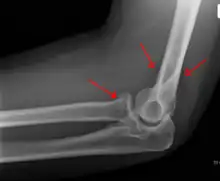

The fat pad sign, also known as the sail sign, is a potential finding on elbow radiography which suggests a fracture of one or more bones at the elbow. It is may indicate an occult fracture that is not directly visible. Its name derives from the fact that it has the shape of a spinnaker (sail).[1] It is caused by displacement of the fat pad around the elbow joint. Both anterior and posterior fat pad signs exist, and both can be found on the same X-ray.

In children, a posterior fat pad sign suggests a condylar fracture of the humerus. In adults it suggests a radial head fracture.

In addition to fracture, any process resulting in an elbow joint effusion may also demonstrate an abnormal fat pad sign. Increased intracapsular fluid is also seen in several conditions other than fracture and this produces the abnormal fat pad sign. (toxic synovitis, septic arthritis, Juvenile Rheumatoid Arthritis, osteomyelitis of the distal humeral physis and secondary septic joint). In these instances, history and clinical examination in addition laboratory results (WBC, ESR, CRP) will guide the provider in determining whether to treat the condition as an occult fracture or continue workup for other pathology.

The fat pad sign is invaluable in assessing for the presence of an intra-articular fracture of the elbow. An anterior fat pad is often normal. However a posterior fat pad seen on a lateral x-ray of the elbow is always abnormal. The patient will be unable to flex their elbow and requires orthopaedic input.[2]

The posterior fat pad is normally pressed in the olecranon fossa by the triceps tendon, and hence invisible on lateral radiograph of the elbow.[3] When there is a fracture of the distal humerus, or other pathology involving the elbow joint, inflammation develops around the synovial membrane forcing the fat pad out of its normal physiologic resting place. This is visible as the "posterior fat pad sign" and is often the only visible marker of a fracture, particularly in the pediatrics population.